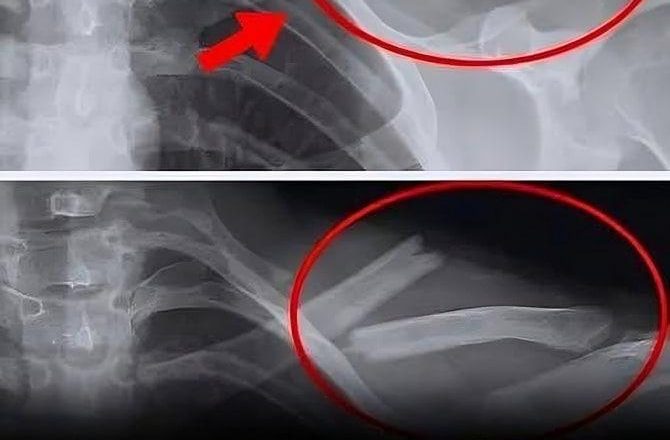

Słabe kości / Osteoporoza

Picie napojów gazowanych zwiększa ryzyko osteoporozy ze względu na działanie kwasu fosforowego, który utrudnia prawidłowe wchłanianie wapnia, osłabiając kości.

Badanie przeprowadzone przez Tufts University wykazało, że u kobiet, które piły napoje gazowane trzy razy w tygodniu, zaobserwowano średnio o 4% większą utratę tkanki kostnej (w obszarach takich jak biodra) niż w grupie kobiet spożywających inne rodzaje napojów.